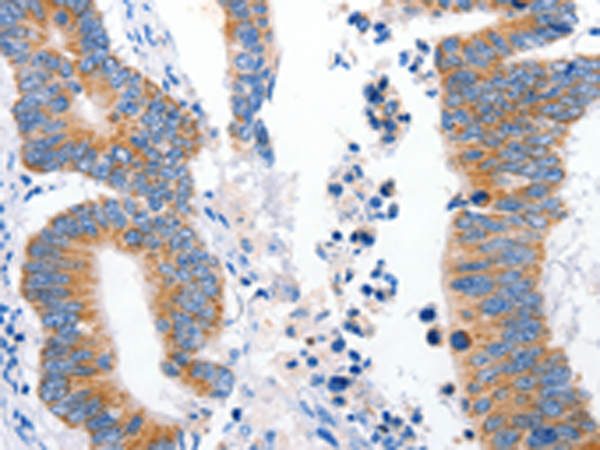

分类: 科研抗体货号: P04109别名: bHLHc2应用: IHC反应种属: Human, Mouse